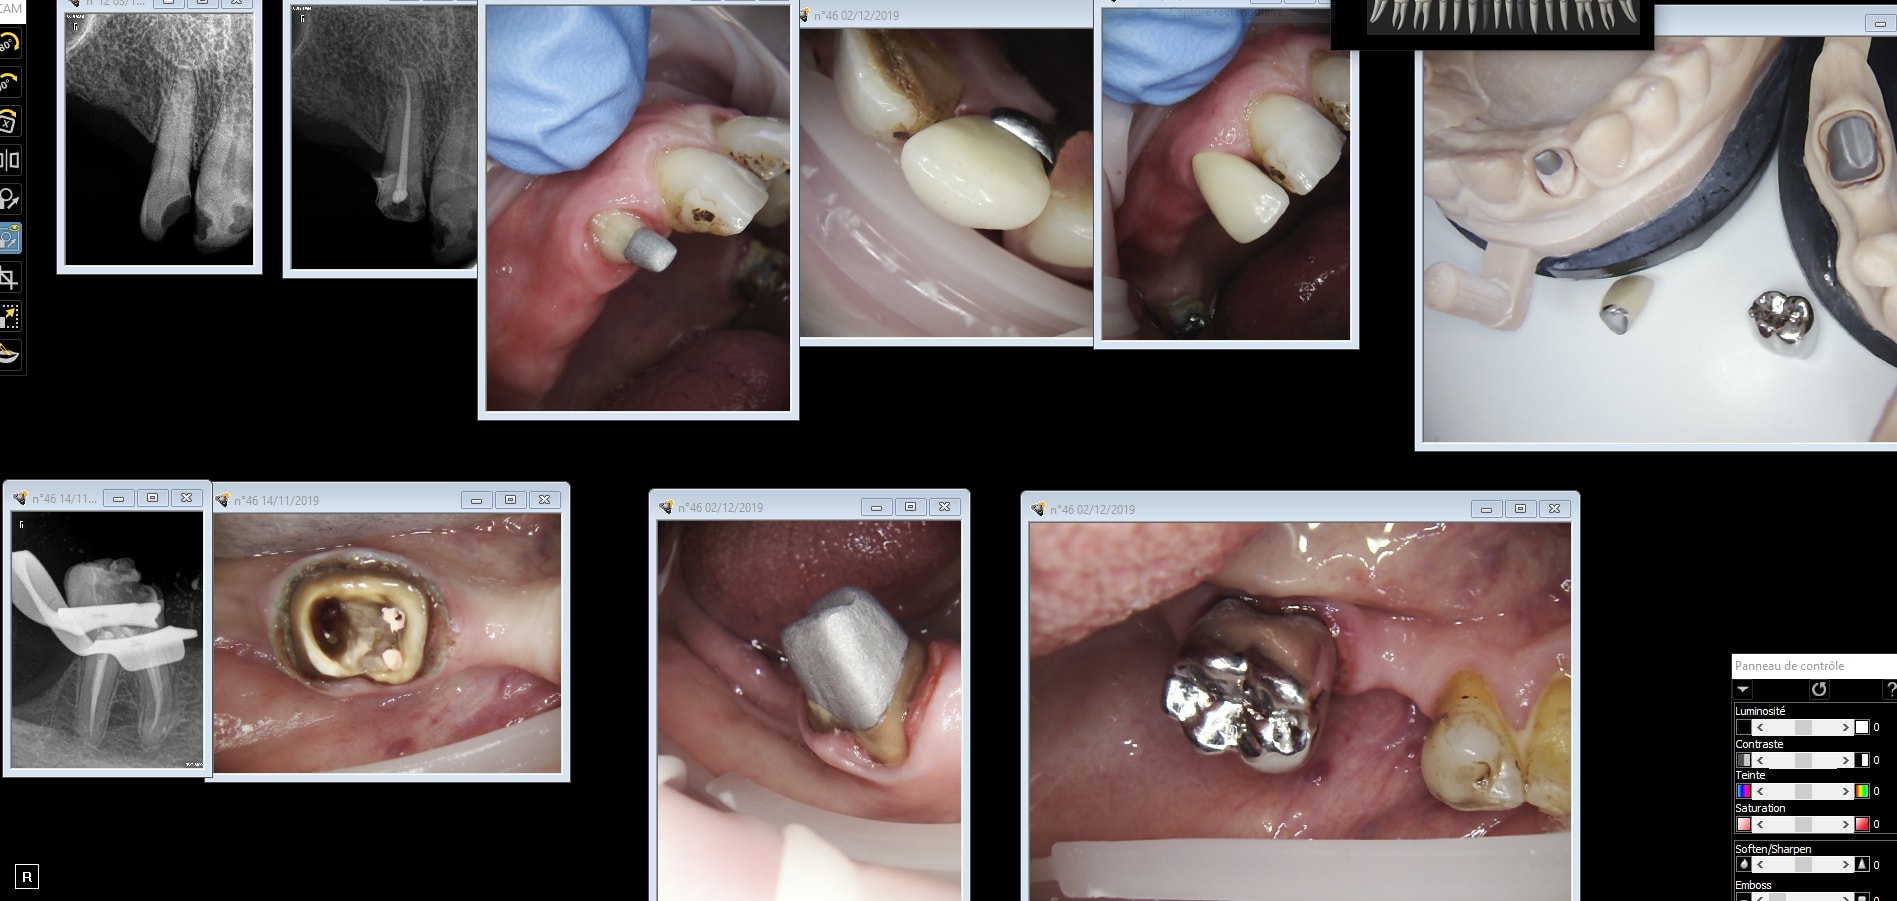

je viens de salement galerer chez un papi pour une endo 37... qui finira en rac0 cc…

La rentabilité horaire des det.

la prochaine c'est extraction + new stellite chinois. Je vais te mettre en marche tout ca moi.

One shot chinetoc. dents manquantes mandibulaires pas RAC 0 Fin de PTT. -)))

Dant 46 12 j1q6ol - Eugenol

Traitement inaccessible si pas RAC 0. -)))